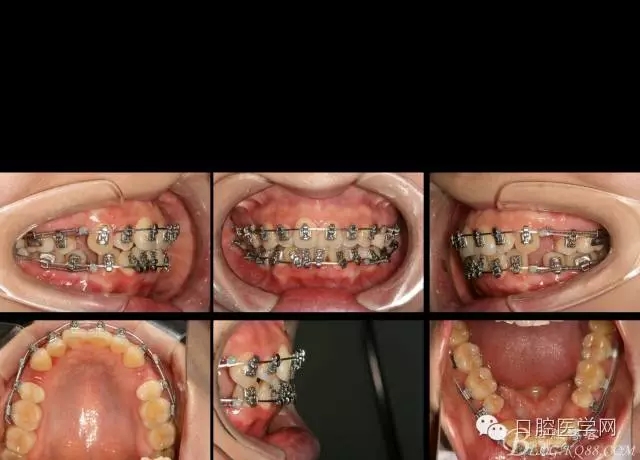

2016.4.8 第一次復診,換為022*016tn扁絲,在上下尖牙遠中用等力拉簧滑動關閉,內(nèi)收前牙。

2016.6.7 第二次復診效果 上頜繼續(xù),只是將弓絲末端變長的弓絲剪斷重新回彎,其他沒有做任何處理。下頜將右側(cè)的拉簧拆掉,在右下1與3之間推簧,調(diào)整中線,其余沒動。

矯正到目前,矯正開始三個月四天,矯正比較平穩(wěn),拔牙間隙關閉接近三分之二。矯正效果明顯。每次復診處理簡潔,椅旁時間幾分鐘。大大減少醫(yī)生工作壓力,矯正療程大大縮短,是個很好的技術。

如果,矯正再輔助種植支抗,穩(wěn)定主弓絲平面以及轉(zhuǎn)移牽引力,矯正將更加平順穩(wěn)定。